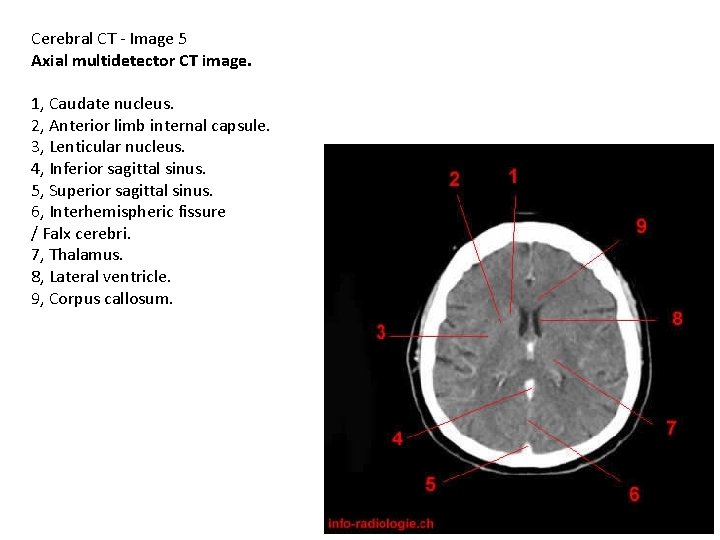

Cerebral CT - Image 5 Axial multidetector CT image. 1, Caudate nucleus. 2, Anterior limb internal capsule. 3, Lenticular nucleus. 4, Inferior sagittal sinus. 5, Superior sagittal sinus. 6, Interhemispheric fissure / Falx cerebri. 7, Thalamus. 8, Lateral ventricle. 9, Corpus callosum.